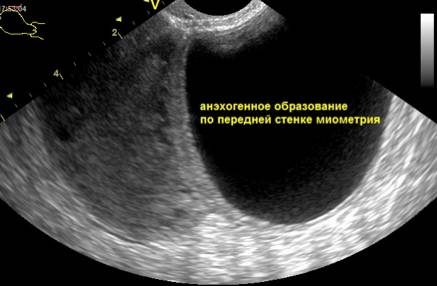

На экране ультразвукового аппарата анэхогенные образования выглядят как темные участки, иногда с неоднородным цветом, что зависит от их содержания (кровь, жидкость, ткань).

| Подслизистая миома матки | УЗИ, МРТ: анэхогенное или гипоэхогенное образование в миометрии, может деформировать полость матки. | Миомэктомия (хирургическое удаление), эмболизация маточных артерий (ЭМА), медикаментозная терапия (в зависимости от размера и симптомов). |